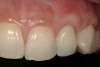

From a clinical perspective, the primary challenge was the development of an esthetic emergence of the dental implant-supported crown restoration. Maintenance of the soft-tissue dimensions, therefore, was critical to the treatment success. In an effort to optimally maintain the ridge form, a connective tissue graft harvested from the palate39,40 was placed over the collagen membrane to augment the soft tissues. Then, the buccal flap was advanced to achieve primary closure. Postoperative healing proceeded uneventfully. The overlying soft tissue exhibited rapid clinical closure and healed with minimal evidence of the surgical procedure. The clinical outcome was also consistent with development of the desired ridge form. Cone-beam computed tomography imaging revealed an alveolar ridge form that was optimal for implant placement at 5 months post-treatment. The radiographic density of the augmented region was similar to the adjacent native bone, with no discernable interface between native and apparent new bone, consistent with integration and remodeling. Surgical re-entry for implant placement revealed the optimal ridge form (Figure 6 ). The implant was allowed to integrate for 5 months prior to the healing abutment placement and interim restoration. The overcontoured soft tissues enabled surgical sculpting to achieve the desired contour for the restorative emergence. A highly acceptable esthetic result was achieved. With preservation of the marginal and papillary gingival contours (Figure 7 and Figure 8 ); the radiographic presentation was consistent with normal bone remodeling and implant integration.

Figure 8  Marginal and papillary gingival contours were well preserved using this technique.

Figure 8